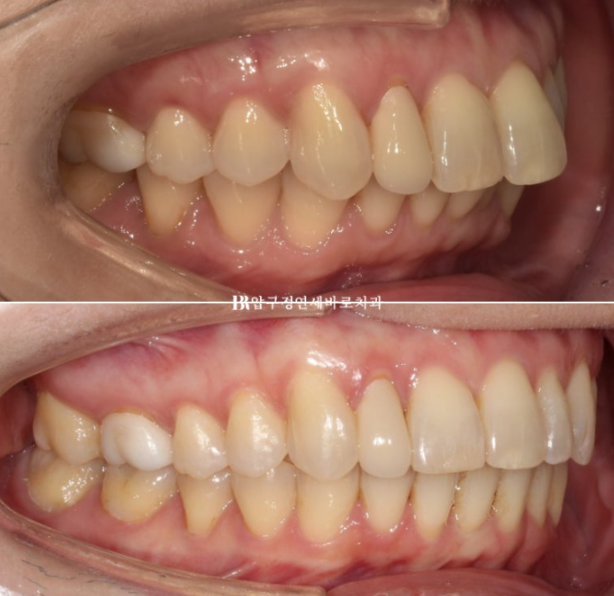

24.02

환자분이 고치고 싶은 것은 환자분 기준 왼쪽 앞니가 내려오고 튀어나온 것 입니다.

윗니가 아랫니를 많이 덮어 깊게 물리는 과개교합이 보입니다.

파란화살표 맨 뒤 큰어금니는 위 아래가 엇갈려 물리는 가위교합 입니다.

측면에서 보면 앞니 돌출이 보입니다.

치료 전 후 보겠습니다.

좌 - 치료 전 / 우 - 치료 후

24.02~24.12

치간삭제를 통한 앞니 돌출감 개선

앞니 배열 개선과 가위교합 개선